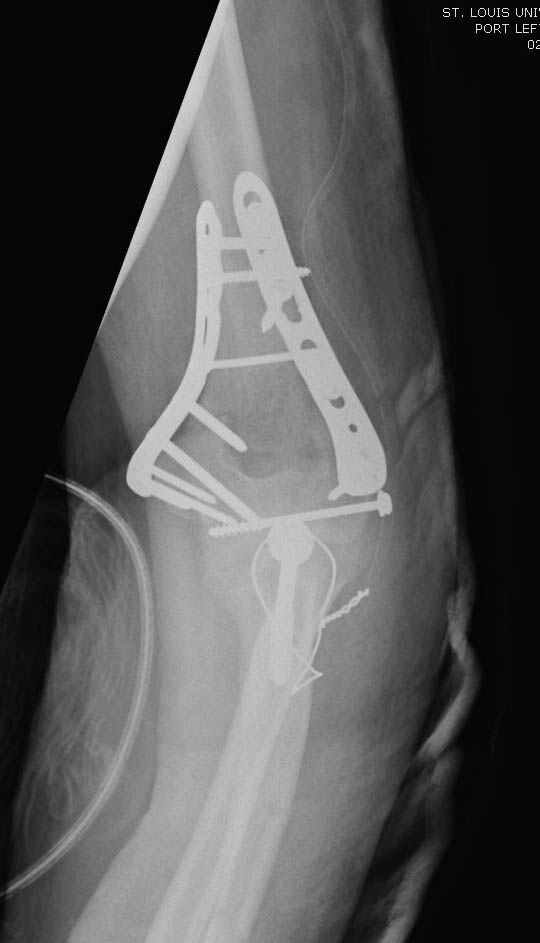

Солидарен с мнением обоих Александров (Челнокова и Рыкова): точную репозицию такого перелома вряд ли удастся выполнить закрыто. Даже во время открытого вмешательства это сделать непросто. Неслучайно предложен костно-пластический доступ с временным отсечением локтевого отростка. И по методу фиксации согласен с Александром Челноковым: 2 пластины. В качестве примера привожу рентгенограммы одного из наших пациентов с аналогичным повреждением.

С уважением, А. Золотов, Приморский край.

Djoldas Kuldjanov, M.D. 09 Сентябрь 2005, 20:07

Примерный случай, только перелом был открытый, в задне-медиальной стороне рана около 2 см по характеру "изнутри кнаружи", неврологический статус со слабостью сгибания мизинца, также слабая абдукция и аддукция указательного пальца и сгибания в кисти.

Больному сделали обработку и наложили временный аппарат внешной фиксации плечо-предплечье.

На шестой день сделали открытую репозицию чрезлоктевым доступом двумя locking plate, локтевой нерв был ушибленным, после операции положительная динамика в Flexor Carpi Ulnaris. Фиксацию локтевого отростка произвели tension band technique с дополнительным шурупом.

Этапы операции на снимках....

Джолдас Кульджанов

Djoldas Kuldjanov, MD

Department of Orthopedic Surgery

St. Louis University Medical Center